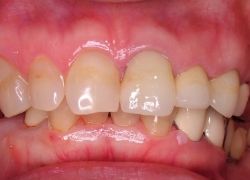

④術後経過例:徐々に歯周炎の症状が改善してきています.レーザー治療を続けながら,部分矯正(歯冠部が欠け,歯根だけになった部分の牽引矯正)を行っています.

・レーザー治療後(写真右)

:歯周基本治療との併用で炎症改善.

⑤治療後:慢性の歯肉炎症が改善し,全体的に引き締まって健康なピンク色に近づきました.この状態でオールセラミックス製のクラウン冠をかぶせて審美治療を行いました.この冠は,金属を必要としない最新の方法で,従来のように金属の色が透けて歯と歯ぐきのさかい目が黒ずむという心配はありませんので,歯肉もより自然の色に見えます.

[歯周病菌の検査]